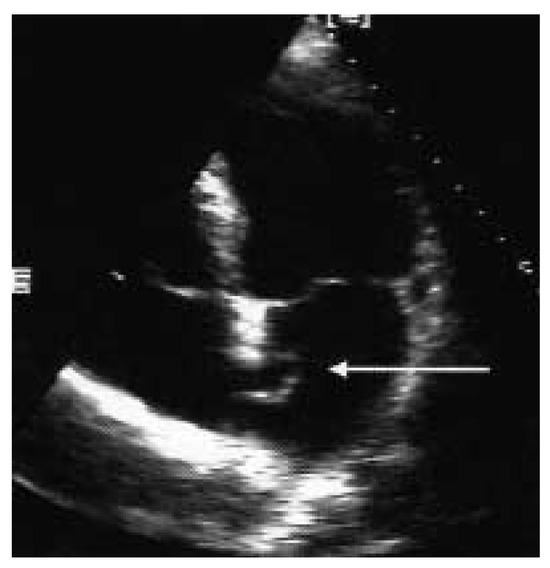

Epanchement Péricardique

by Jürg Schläpfer

Description du cas Patiente de 48 ans, éthylo-tabagique, présentant un état grippal récent avec exacerbation d’une toux chronique qui motive l’hospitalisation [...] Full article